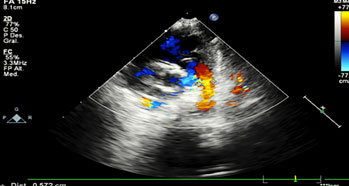

Neurológico: hipoactivo, reactivo a estímulos externos, con fontanela anterior normotensa, la posterior amplia. Al décimo día, crisis convulsivas focalizadas a miembros superiores, se agrega anticomisial, ultrasonido trasnsfontanelar normal. La frecuencia cardiaca con 42 a 65 latidos por minuto, precordio hiperdinámico, soplo sistólico en 2° Espacio Intercostal Izquierdo grado II/VI, sin irradiación, con 2do ruido intenso, borde hepático a 3 cm por debajo de reborde costal, pulsos amplios en las 4 extremidades, simétricos, ameritó apoyo aminérgico y noradrenérgico, persistiendo con bradicardia, por hipertensión arterial sistémica se suspende. El ecocardiograma reportó CIV perimembranosa de 2 mm, CIA de 6 mm ostium secundum, PCA de 5x6x5 mm, insuficiencia tricuspídea moderada y se envía a 3er nivel (figuras 3, 4 y 5). Desafortunadamente no se autorizó autopsia.